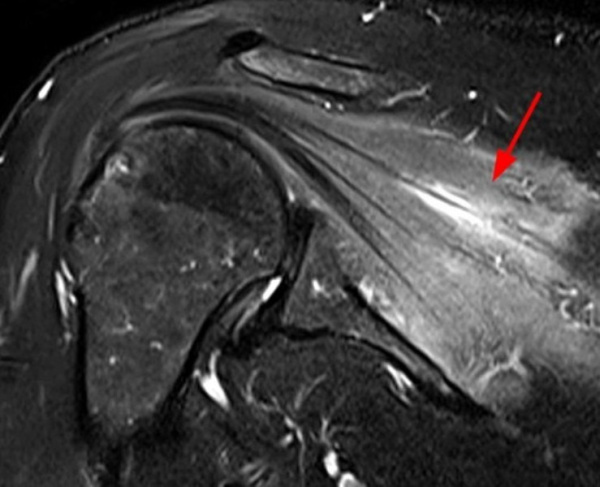

- Магнитно-резонансная томография. МРТ позвоночника проводится для исключения радикулопатии, вызванной грыжей межпозвоночного диска. На МРТ мягких тканей с усилением гадолинием визуализируются участки высокой интенсивности сигнала, соответствующие воспалению в нервных волокнах.